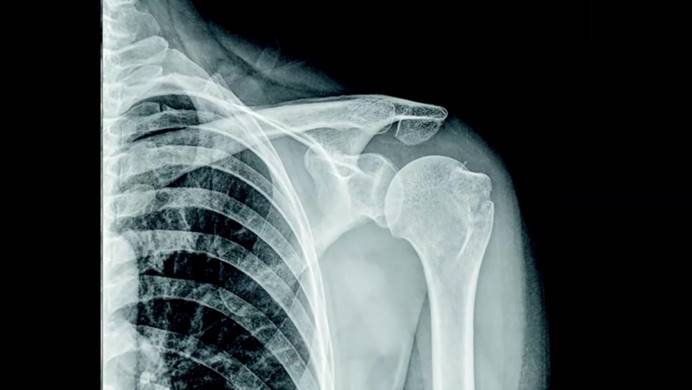

微小細節往往是正確診斷的關鍵。在事故及緊急情況下,高質量X射線圖像對患者至關重要,這就是為什么AGFA對其生產的設備要求特別嚴格。借助蔡司解決方案不僅獲得高質量及可靠的檢測結果,測量時間更是降低了90%。

為數字X射線成像技術制造光盤時,面臨的挑戰之一就是光盤的平面度,越理想的光盤平面越可以確保呈現的圖像可靠詳細。光盤的質量會影響圖像呈現的信息,圖像里的模糊區域會使得診斷變得更加困難,在極端情況下,醫生可能會看不到骨折和腫瘤,存在潛在風險。

▌高質量X射線圖像